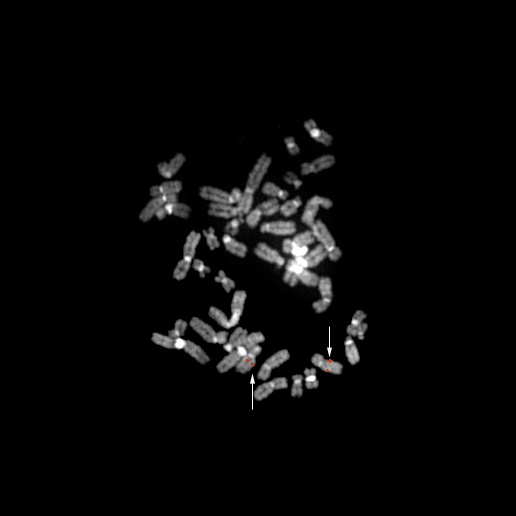

bA441M8